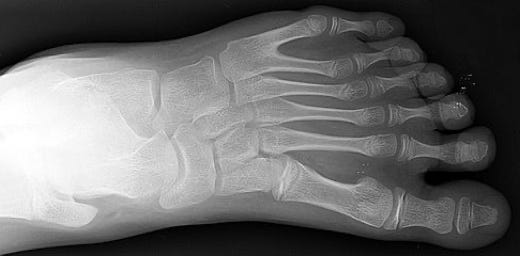

Henry II the Pious (1196??-1241) was Duke of Silesia and High Duke of Poland. He was married to Anna of Bohemia who was the daughter of King Ottokar I of Bohemia, and they had ten, some say even eleven children. In January 1241 Poland was invaded by the Mongols commanded by Orda Ichen, who after ravaging Rus decided to attack Hungary via Poland. Henry II, after being refused help by Emperor Frederick II and King Bella IV of Hungary decided to concentrate his troops near the town of Legnica in western Poland. The battle of Legnica took place on 9th of April 1241 and the Polish army was soundly defeated and Duke Henry II was killed and beheaded. His headless and naked body was so badly mutilated that later it could only be identified by his wife. Some may wonder how could a wife who bore at least 10 children to her husband identify his mangled body? And, yes, while your line of thinking may sometimes bear fruit, it wasn’t that you dirty scoundrels. He lived 800 years ago, there was no electricity in those days, procreation was performed in complete darkness, hence the name the Dark Ages. She was able to tell her husband apart from the other corpses not because of his middle leg, but because of his polydactyly. Now, what kind of a bird is polydactyly? Actually it’s not a bird, but an additional finger or toe that some people happen to have on their bodies. And Henry happened to have six toes on his left foot.

The fact that he indeed had six toes on his left foot was corroborated in 1832 when his tomb was opened. After that his remains were buried in the Franciscan Church of Sts Vincent and Jacob in Wrocław (in those days called Breslau).